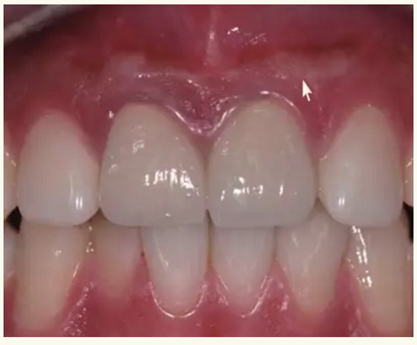

▲ 術(shù)前,21唇側(cè)牙齦距離齦緣2mm處及瘺管

▲牙膠尖示蹤顯示瘺管與此相通

▲21牙根近中側(cè)位于根尖1/3和根中1/3交界處有牙周膜間隙略增寬

▲術(shù)后,手術(shù)切口處疤痕

▲術(shù)后,X線顯示:21根尖切除區(qū)域骨質(zhì)修復(fù),根管倒充填物完好,原牙周膜間隙增寬影消失